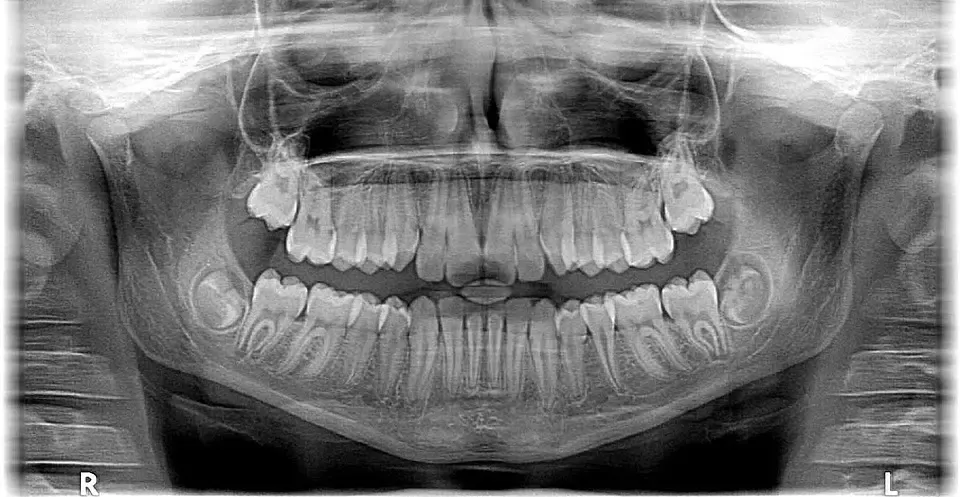

Dober ortodont v Velenju poskrbi za klinične preglede in tudi natančne analize

rentgenskih posnetkov ter izdela kvaliteten načrt zdravljenja in

vzdrževanja zobovja.